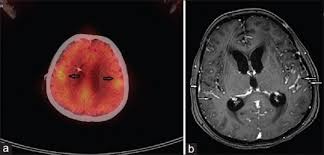

Intracranial Leptomeningeal Carcinomatosis In Three Cases From Breast Cancer Demonstrated On F 18 Fluorodeoxyglucose Positron Emission Tomography Computerized Tomography Abstract Europe Pmc